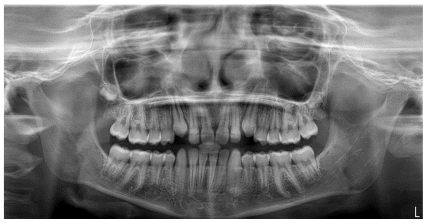

The patient was a young female presenting with a Class III dento-skeletal malocclusion, which was treated using the AMCOP® TC appliance. A comprehensive diagnostic protocol was carried out both before and after treatment, including orthopantomography (Figure 2–3), postero-anterior teleradiography (Figures 4, 5), latero-lateral cephalometric radiography (Figures 6, 7), cephalometric analysis (Tables 1, 2), as well as extraoral (Figures 8, 9) and intraoral photographs (Figures 10, 11). The extraoral examination revealed an edge-to-edge incisal relationship and the presence of a midline diastema. Pre-treatment cephalometric analysis (Deltadent® Lana, Bolzano, Italy) confirmed the diagnosis of a skeletal Class III malocclusion. The treatment plan involved the use of the AMCOP® TC appliance. The patient was instructed to wear the device for two hours in the afternoon and throughout the night for the first six months, followed by nighttime use only for an additional six months. Upon completion of the treatment, the patient achieved a Class I occlusion, with correction of both overjet and overbite. Additionally, the device facilitated tongue re-education and contributed to the postural realignment of the first cervical vertebra.